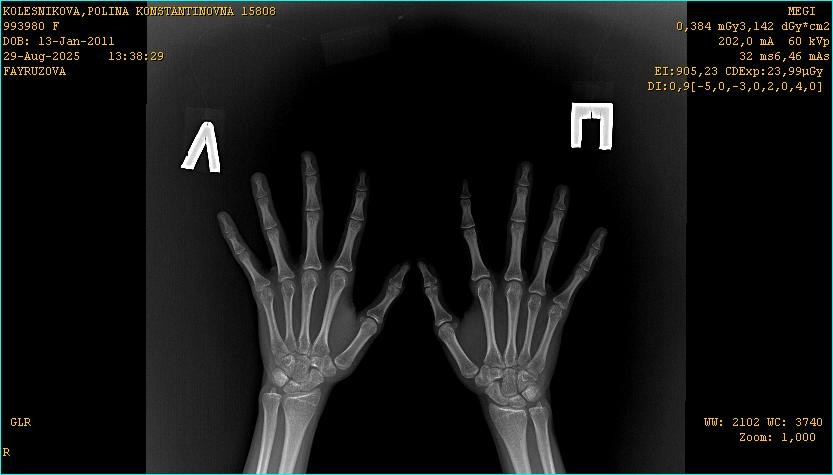

Здравствуйте, девочка 14 лет. Подскажите пожалуйста открыты ли еще зоны роста. По ренгену костный возраст на 16 лет